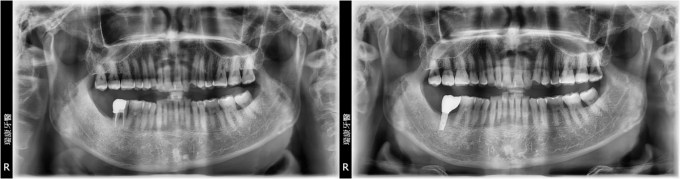

病患莊先生,35年次,退休人員

- 主訴:右下後牙咬東西時劇痛

- 口腔檢查: 右下牙齒斷裂

- 治療計劃: 將右下後牙拔除後,等待三個月癒合期,進行人工植牙, 三個月後接出假牙基座印模製作正式假牙!

實例照片僅為資訊介紹及分享,效果可能因個人體質及保養方式不同而有所差異。